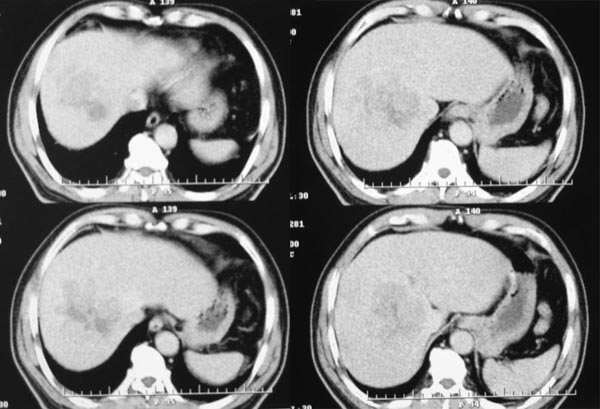

延时期

综上所述,符合肝癌伴下腔静脉癌栓形成

早期强化不是很明显,血供不是很丰富,与肝实质相比还是呈快进快出的特点,中心裂隙样坏死,支持原发性肝癌。

平扫:团块状低密度灶,动脉期:边缘环形强化,门脉期:增强逐步向中心推进,实质期:强化进一步明显,中心呈裂隙样无强化影。所以首先考虑血管瘤

支持肝癌诊断的为什么不说延迟期病灶的表现呢?